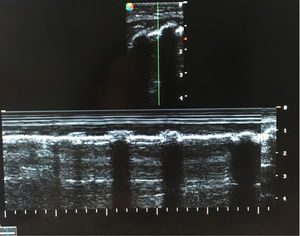

Paciente de 4 meses de edad, exprematuro de 24 semanas de gestación y con displasia broncopulmonar grave, conectado a ventilación mecánica (modalidad presión control con PIP 25cmH2O, PEEP 5,5cmH2O, FR 35rpm y FiO2 30%). El día que describimos, el paciente precisaba FiO2 de hasta el 50% y en la radiografía de tórax (fig. 1) mostraba hiperinsuflación intensa del hemitórax derecho y ausencia de deslizamiento pulmonar en la ecografía pulmonar (fig. 2). Dada la evolución de los pacientes con displasia broncopulmonar hacia la compresión dinámica de la vía aérea distal, se decidió incrementar progresivamente PEEP, sin mejoría ecográfica hasta llegar a una PEEP de 10cmH2O, donde se evidenció reaparición del deslizamiento pleural (fig. 3), y en la radiografía de tórax resolución parcial de la sobredistensión (fig. 4).